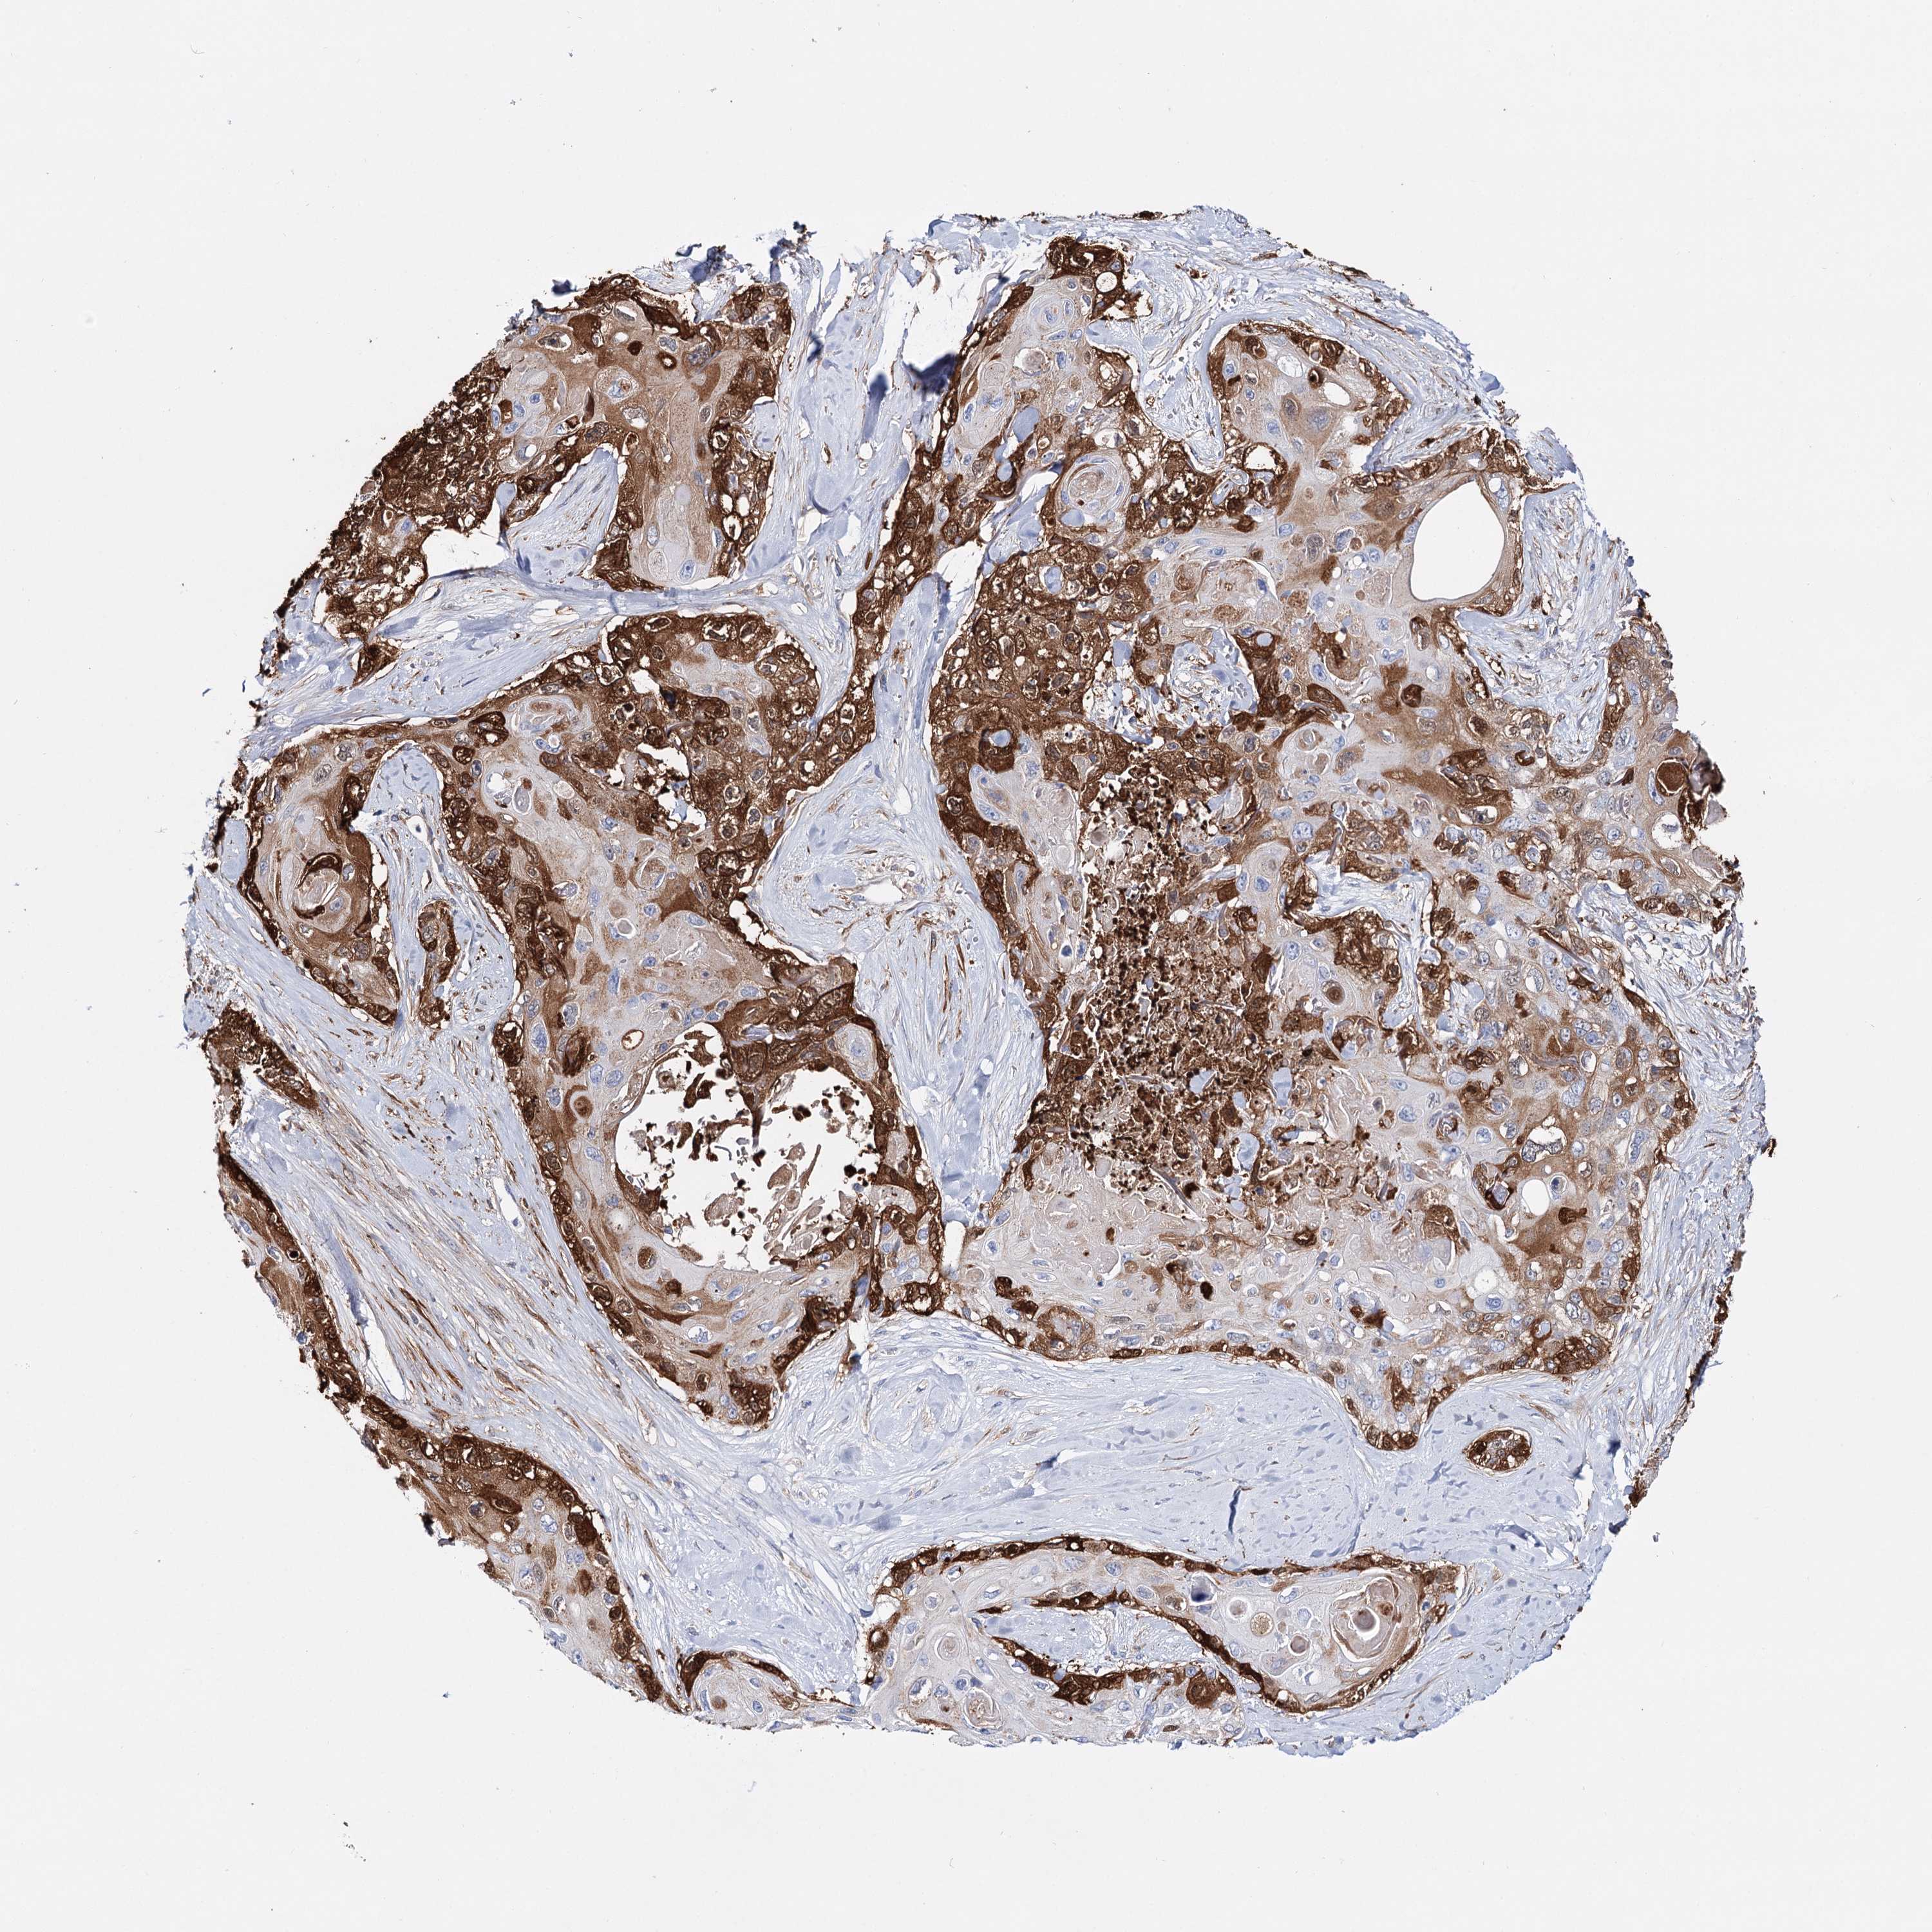

SKIN CANCER - Protein expressioni

A mouse-over function shows sample information and annotation data. Click on an image to view it in a full screen mode. Samples can be filtered based on level of antibody staining by selecting one or several of the following categories: high, medium, low and not detected. The assay and annotation is described here.

Antibody stainingi

Antibody staining in the annotated cell types in the current human tissue is reported as not detected, low, medium, or high, based on conventional immunohistochemistry profiling in selected tissues. This score is based on the combination of the staining intensity and fraction of stained cells.

Each image is clickable and will lead to virtual microscopy that enables deeper exploration of all samples and also displays staining intensity scores, fraction scores and subcellular localization as well as patient and tissue information for each sample.

Antibody HPA037786

Antibody HPA038034

Antibody HPA038867

Antibody HPA038868

High

Strong

>75%

Cytoplasmic/membranous

Squamous cell carcinoma, NOS